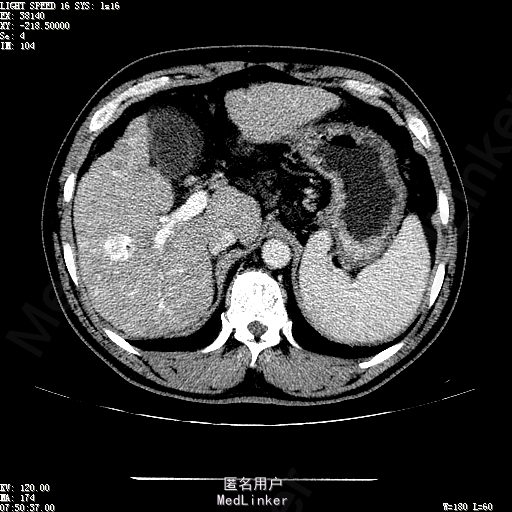

主诉:肝癌TACE治疗后36天 病史:患者两年前体检发现丙型肝炎病毒标志物阳性,于当地医院就诊诊断为"丙肝肝硬化",口服药物治疗,具体用药不详。定期复查肝功及肝脏影像学检查,2月前于医大二院行肝脏增强磁共振检查发现肝S6段动脉期增强结节,36天前在我院行DSA肝动脉造影明确"原发性肝癌"诊断并行"TACE"治疗,术后恢复良好,现患者为进一步行肝癌局部消融治疗来诊。

诊断:1、丙肝肝硬化 代偿期;2、原发性肝癌 S5段、S6段 该患诊断明确,既往曾行TACE治疗肝癌,S5段、S6段近右肾上极2处碘油沉积明确,S5段者较大,约2.31cm。超声显示清晰,为防止癌灶复发,适合行射频消融治疗。